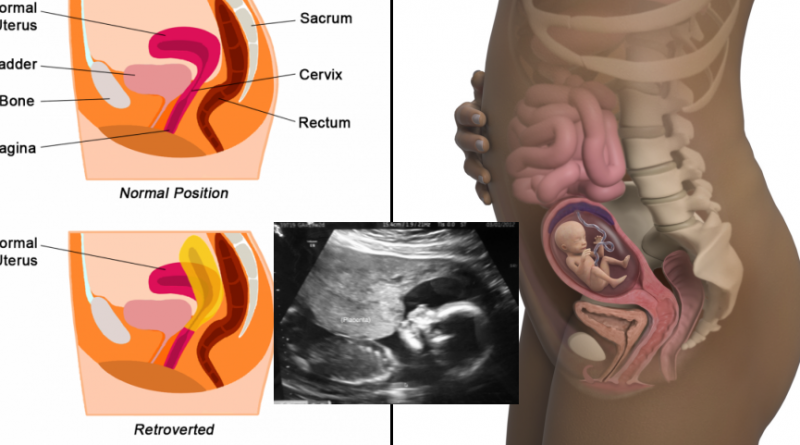

Rahim jadi organ reproduksi yang vital bagi cewek sebagai wadah tumbuhnya janin setelah pertemuan sperma dan ovum. Posisinya berada di tengah rongga panggul yakni bertepatan dengan perut bagian bawah. Di bagian depan terdapat kandung kemih dan di belakang rahim terdapat rektum. Bentuknya mirip buah pir yang ukurannya sekepalan tangan. Struktur ototnya sangat kuat sehingga bisa meregang berkali-kali lipat dari ukuran awal sesuai dengan ukuran janin saat hamil.Posisi atau letak rahim antara cewek yang satu dengan yang lainnya nggak selalu sama. Meski nggak 100% akurat, bentuk atau pun kemiringan rahim turut memengaruhi kemampuan wanita untuk hamil. Ada baiknya kamu kenali beberapa posisi rahim baik yang normal maupun yang terdapat kelainan berikut.1. Rahim yang normal berada dalam posisi antefleksi dan anteversi. Mayoritas cewek punya rahim dengan posisi seperti iniposisi normal via slideplayer.comNormalnya, rahim berada dalam posisi antefleksi dan anteversi. Pada posisi antefleksi, fundus atau bagian paling atas dari rahim condong ke depan dan ke arah perut. Jadi posisi mulutnya menengadah ke depan.Sedangkan posisi anteversi berarti rahim cenderung lebih terdorong ke depan. Cewek yang letak rahimnya seperti kedua jenis di atas punya peluang yang besar untuk hamil karena akan memudahkan perjalanan sperma menuju sel telur.2. Ada juga yang rahimnya berjenis retroversi dan retrofleksi. Keduanya mengarah ke belakang atau terbalik dari arah yang seharusnyarahim dengan posisi terbalik via www.pinterest.co.ukPada rahim retroversi, letaknya agak condong ke belakang mengarah ke tulang selangkangan namun belum sampai menekuk. Sehingga bagian fundusnya tegak menghadap ke atas. Sedangkan pada rahim retrofleksi, posisi fundusnya sudah berbalik arah sehingga menengadah ke belakang yang juga disebut dengan posisi rahim ‘terbalik’.Pada rahim retrofleksi khususnya, posisi mulut rahim nggak menghadap ke arah kedatangan sperma, sehingga akan kesulitan dalam proses pembuahannya.3. Prolapsus uteri atau rahim yang melorot sehingga menonjol ke vagina atau turun peranakanturun peranakan via healthjade.comPenyebab kelainan letak rahim ini antara lain karena lemahnya jaringan ikat pada rongga panggul atau dampak dari pertolongan persalinan yang kurang terampil, misalnya sudah disuruh mengejan padahal pembukaan belum lengkap. Kondisi ini bisa menimbulkan luka pada jalan lahir yang bisa melemahkan jaringan ikat penyangga vagina.Keluhan utama prolapsus uteri adalah adanya tonjolan di bagian depan vagina yang mengganggu saat beraktivitas. Jika dibiarkan bisa menjadi luka dan berpotensi infeksi.4. Inversio uteri atau posisi rahim yang terbalik ke bawah, biasanya terjadi saat proses persalinan yang keliruinversio uteri via beautifulpleasuredotcom.wordpress.comProses persalinan yang keliru di sini misalnya ketika tali pusar bayi sudah ditarik ke bawah padahal belum terjadi kontraksi rahim. Akibatnya, terjadi pendarahan dan nyeri yang hebat karena letak rahim jadi terbalik. Inversio uteri harus segera ditangani dan dilakukan reposisi secepatnya, jika nggak bisa menyebabkan inversio menahun, komplikasi, operasi pengangkatan rahim hingga kematian.5. Ada juga kelainan yang disebut perut gantung atau letak rahim yang menyebabkan rahim semakin menonjol ke depanperut gantung via manaberita.comKondisi ini biasanya ditemukan pada wanita yang sering melahirkan sehingga jaringan ikat dan otot-otot perut menjadi kendur. Dampaknya akan terlihat nyata saat hamil, di mana bagian perut terlihat lebih condong ke depan dan yang perlu diwaspadai adalah proses persalinan bisa berlangsung lebih lama dan kontraksi rahim juga kurang bagus.Karena rahim punya peranan yang krusial bagi seorang wanita, ada baiknya segera periksakan diri ke ke dokter sedari dini untuk mengetahui posisi rahim, terutama saat sedang menjalani program hamil jika menemukan gejala-gejala yang mencurigakan. Semoga sehat-sehat selalu, ya!Artikel Bermanfaat dan Menghibur Lainnya